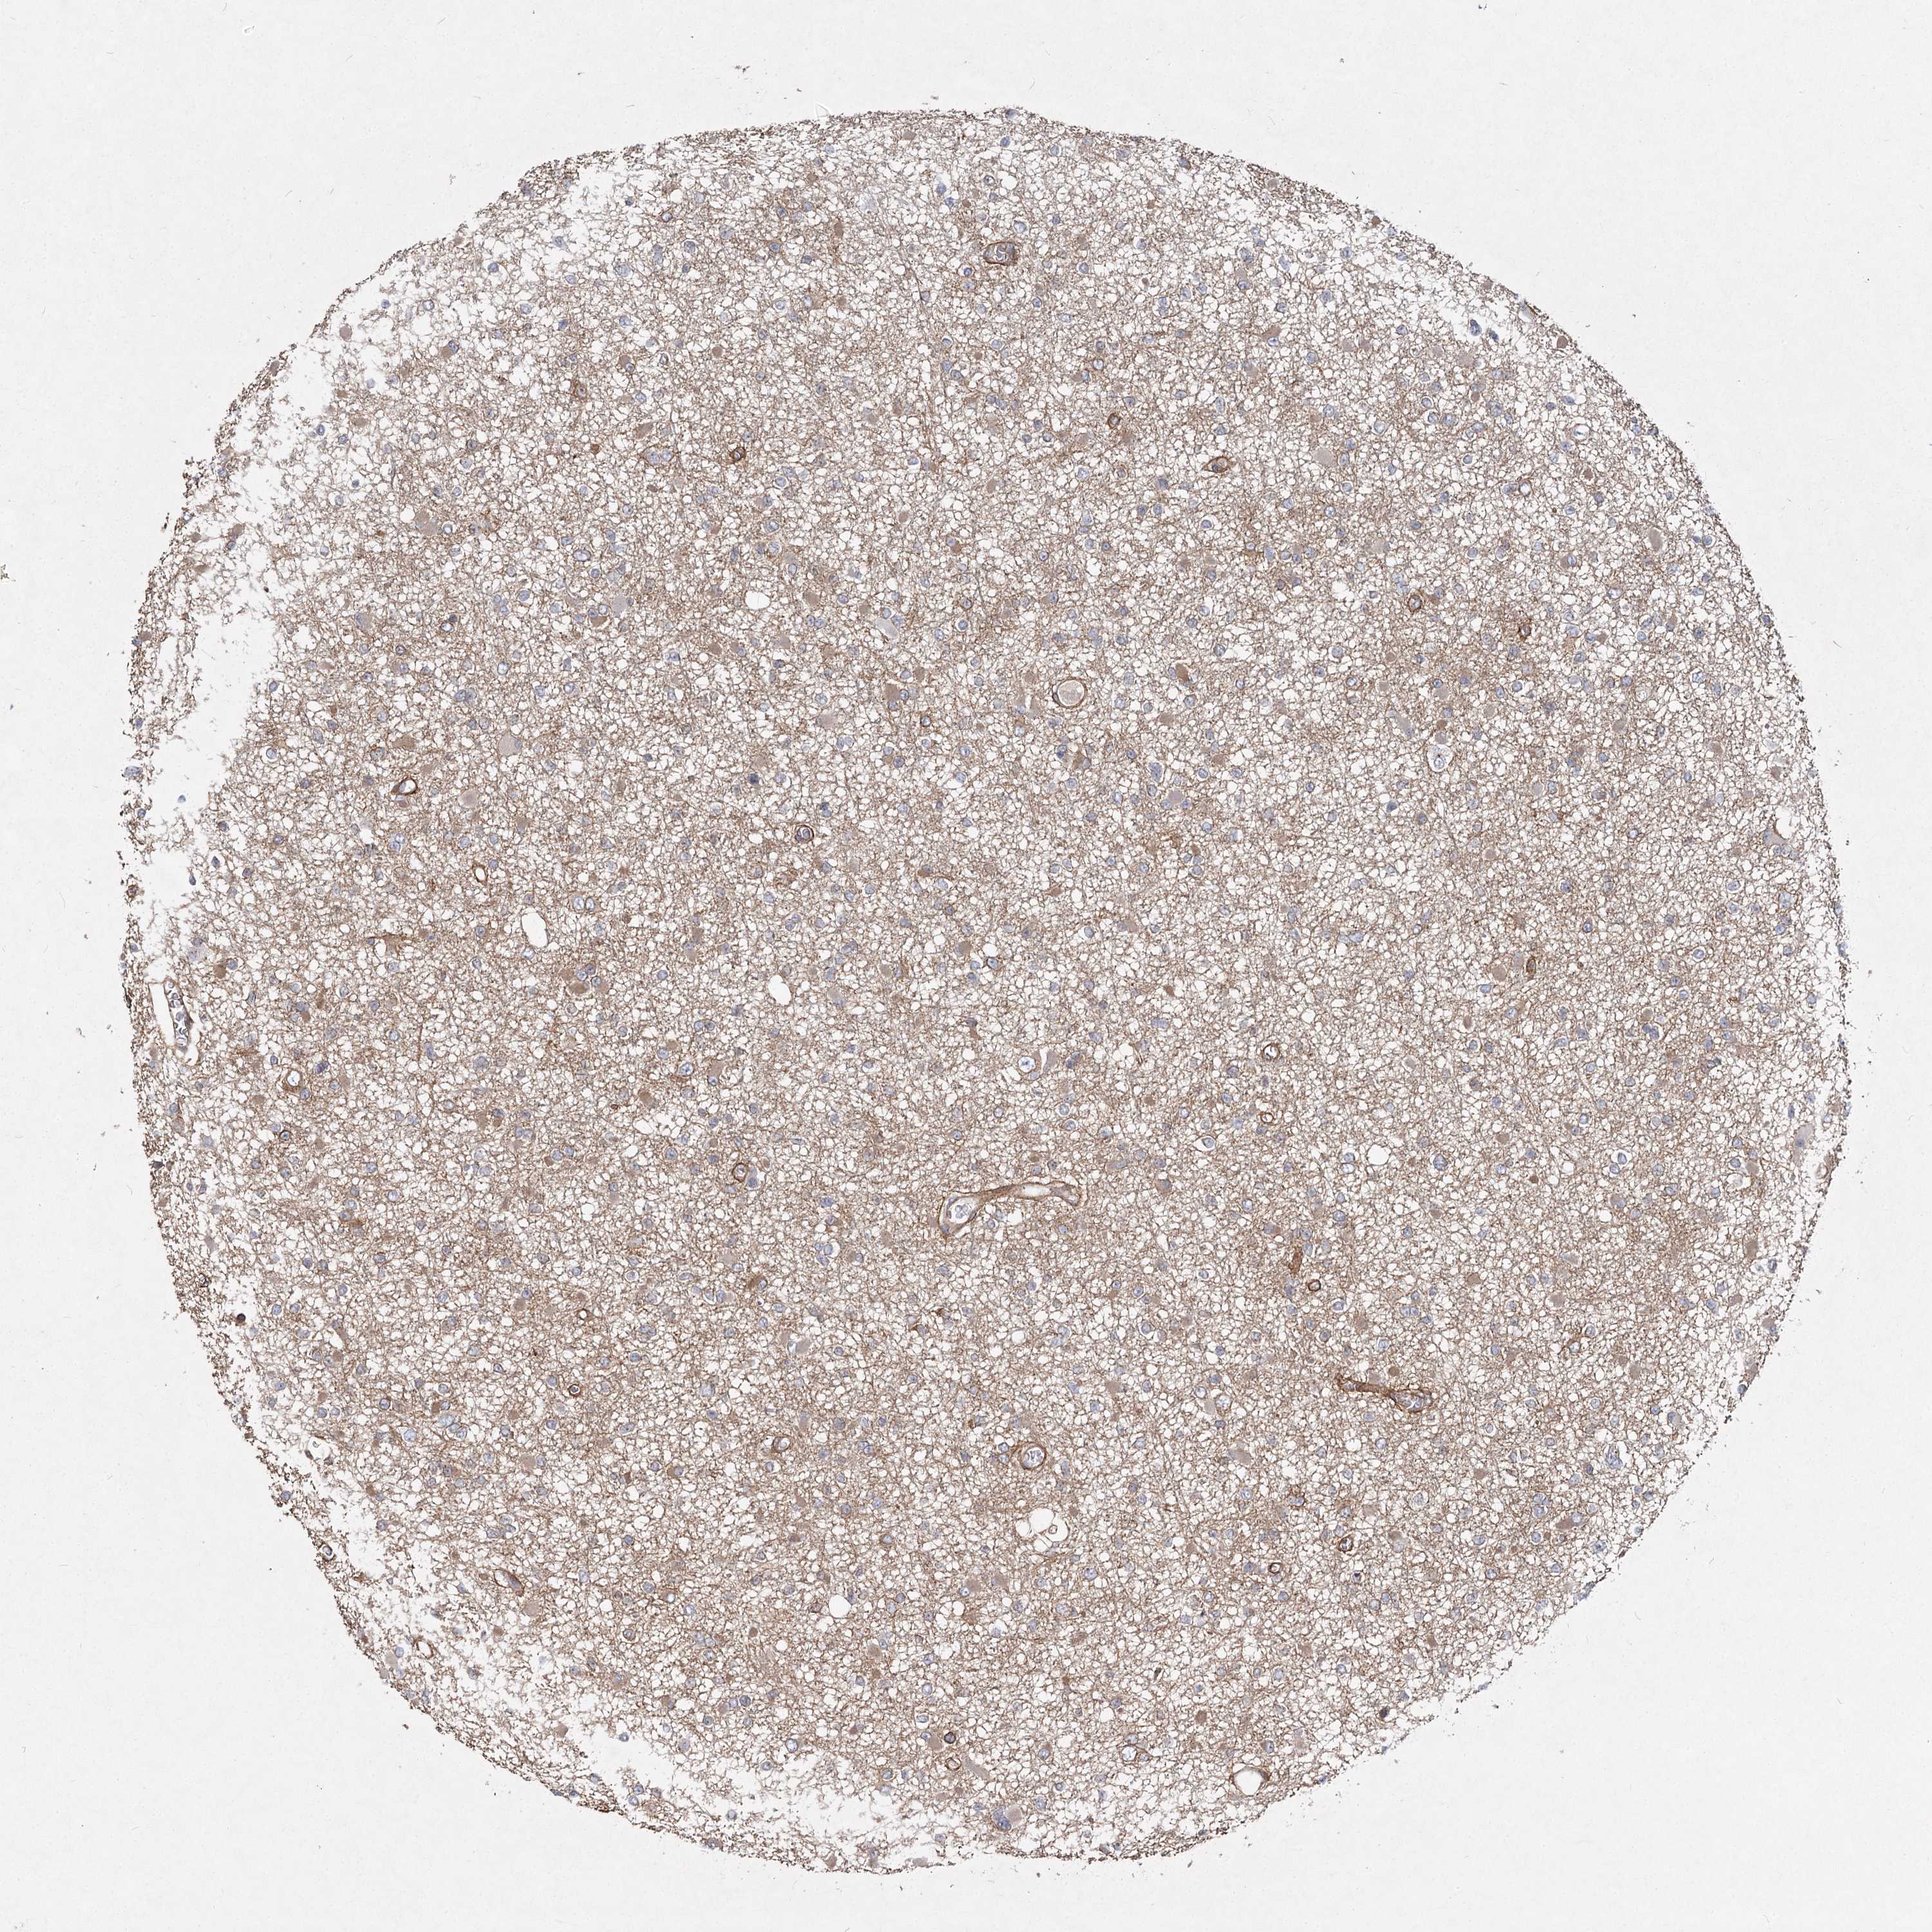

GLIOMA - Protein expressioni

A mouse-over function shows sample information and annotation data. Click on an image to view it in a full screen mode. Samples can be filtered based on level of antibody staining by selecting one or several of the following categories: high, medium, low and not detected. The assay and annotation is described here.

Note that samples used for immunohistochemistry by the Human Protein Atlas do not correspond to samples in the TCGA dataset.

Antibody stainingi

Antibody staining in the annotated cell types in the current human tissue is reported as not detected, low, medium, or high, based on conventional immunohistochemistry profiling in selected tissues. This score is based on the combination of the staining intensity and fraction of stained cells.

Each image is clickable and will lead to virtual microscopy that enables deeper exploration of all samples and also displays staining intensity scores, fraction scores and subcellular localization as well as patient and tissue information for each sample.

Antibody HPA038143

Antibody HPA038144

Staining

High

Medium

Low

Not detected

Intensity

Strong

Moderate

Weak

Negative

Quantity

>75%

75%-25%

<25%

None

Location

Nuclear

Cytoplasmic/membranous

Cytoplasmic/membranous,nuclear

Glioma, malignant, High grade

Glioma, malignant, Low grade

Glioblastoma, NOS